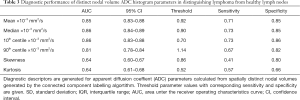

Test results—global ADC

The mean values and SD of tDV and gADC parameters calculated for each patient are shown in Table 1. We found that the mean, median, 10th and 90th centiles gADC values were significantly lower in malignant than in normal lymph nodes. By contrast, ln(tDV), gADC skewness and kurtosis were significantly larger in lymphoma. The gADC SD, IQR, minimum and maximum gADC showed no significant difference between malignant and normal lymph nodes (each P>0.052).

Table 2 shows the performance of the significant gADC discriminators. The order of the diagnostic accuracies of gADC parameters by AUC performance from highest to lowest was: 10th centile, mean, median, 90th centile, skewness and kurtosis. Figure 2 visualises the overlap of gADC parameters between lymphoma and healthy individuals. There was no significant difference of AUC between mean and median gADC, 10th and 90th centile gADC (each P>0.131). Mean gADC AUC was significantly larger than gADC skewness AUC (P=0.032) and gADC kurtosis (P=0.004). 10th centile and median gADC AUC were significantly larger than for gADC kurtosis (each P<0.010). Median and 90th centile gADC AUC were significantly larger than for gADC skewness (each P<0.043). In correspondence to the AUC, the highest Youden index among gADC histogram parameters was calculated for the 10th centile gADC at a threshold of 0.67×10−3 mm2/s, smaller values identifying disease with 91% sensitivity and 95% specificity. A median gADC value less than 0.91×10−3 mm2/s identified disease with 87% sensitivity and 95% specificity. 81% sensitivity and 95% specificity was shown for a threshold mean ADC value of 0.95×10−3 mm2/s. Sensitivity of the 10th centile cut-off was significantly larger than for the mean gADC cut-off (P=0.046). Exemplar maximum intensity projections delineating lymph nodes of a lymphoma patient and a healthy volunteer are demonstrated in Figure 3. Figure 4 visualises the corresponding gADC histograms of lymphoma and healthy nodes of this particular patient (A) as well as the ADC distribution across all study subjects in both groups (B). No gADC parameter showed significant difference between different lymphoma subtypes (each P>0.324).

Regional nodal volumes

In total 307 diseased nodal volumes were identified in the lymphoma patients and 1,002 healthy individual nodes were identified in the volunteer group by the connected component labelling algorithm. Table 3 shows the diagnostic performance of the ADC parameters derived from distinct nodal volumes, which differed significantly between the two groups. In contrast to the corresponding gADC parameters, distinct nodal min and max ADC were significantly lower in lymphoma. The order of diagnostic accuracies of the parameters as indicated by the AUC from highest to lowest was: median and 10th centile, mean, min, 90th centile, skewness, kurtosis and max ADC. Violin plots demonstrating the distribution of parameters calculated for individual diseased/healthy distinct nodal volumes are compared in Figure 5. The natural logarithm of nodal volume, ln(tDV), showed the highest Youden index—a threshold of 0.08 (representing a 1.08 mL nodal volume), resulting in 75% sensitivity and 91% specificity.